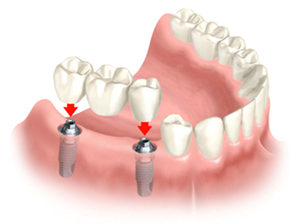

img1 img2

Different parts of regular tooth implant Single tooth and implant supported bridge

Different parts of an Implant prosthesis:

1. The implant: which is made of titanium, is placed in the upper or lower jawbone.

2. The abutment: it can be made of titanium, gold or porcelain. It is attached to the implant with a screw. This part connects the implant to the crown.

3. The restoration:  This is what one sees in his/ her mouth.

1. For single missing tooth it is a crown,  usually made of porcelain fused to a metal alloy (PFM), but also could be an full metal or porcelain crown.

2. For multiple adjacent missing case, it is a bridge made of PFM, full metal or porcelain.